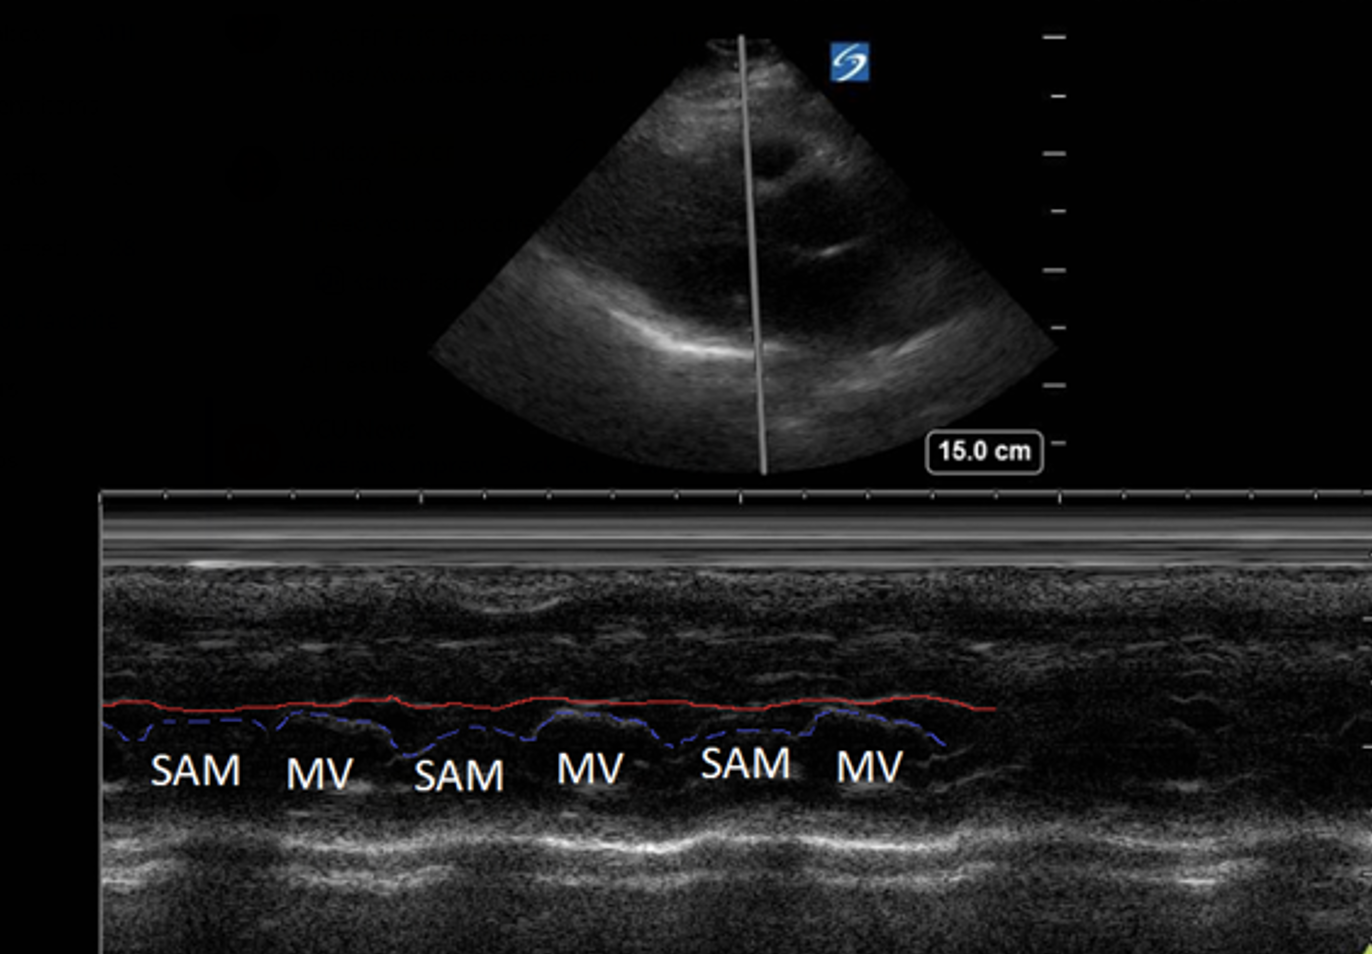

Finding #3: Systolic anterior motion (SAM) of mitral valve

View: PSL View with M Mode, place axis as if you were measuring EPSS at tip of mitral valve

• During systole, the mitral valve should be closed. But in HCM, the mitral valves actually move anteriorly during systole. This can be visualized by using M-Mode.

• This finding used to be pathognomonic for HCM but recent studies have found that only 25-50% of HCM patients with SAM have LVOTO

• The time the mitral valve is in contact with the septum can classify disease severity:

• Mild: brief SAM without septal contact

• Moderate: septal contact is < ⅓ of systolic period

• Severe: septal contact is > ⅓ of systolic period

• Notably, you will also see mitral regurgitation on ultrasound as well

This is the M Mode on the PSL View of a heart with HCM. Notice how you see the opening of the mitral valve in diastole (valve touches the septum), BUT you see the mitral valve moving anterior during systole (arrows).

This is another example of SAM on a HCM patient.

We used M Mode on the mitral valve and did not see SAM.